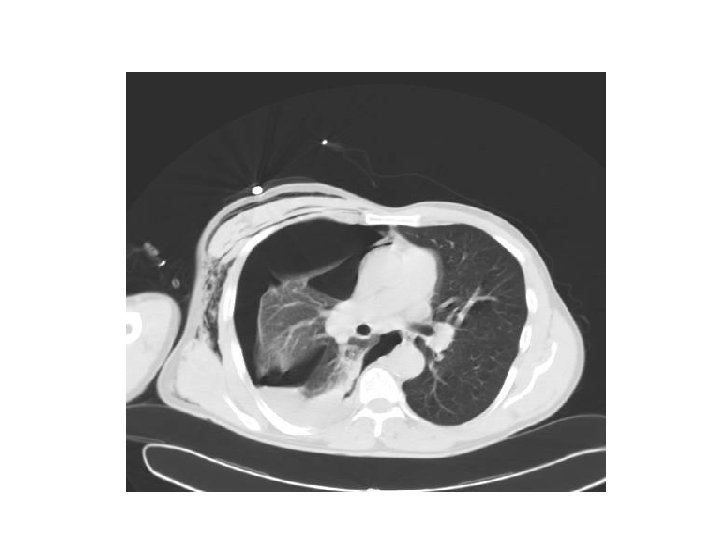

Cas clinique 2 • • • M O. , 55 ans, douleur thoracique droite, brutale, non fébrile tabagisme à 50 PA, sevré il y a 1 an diminution du murmure vésiculaire crépitement sous cutané

• Diagnostic ? • Traitement ?